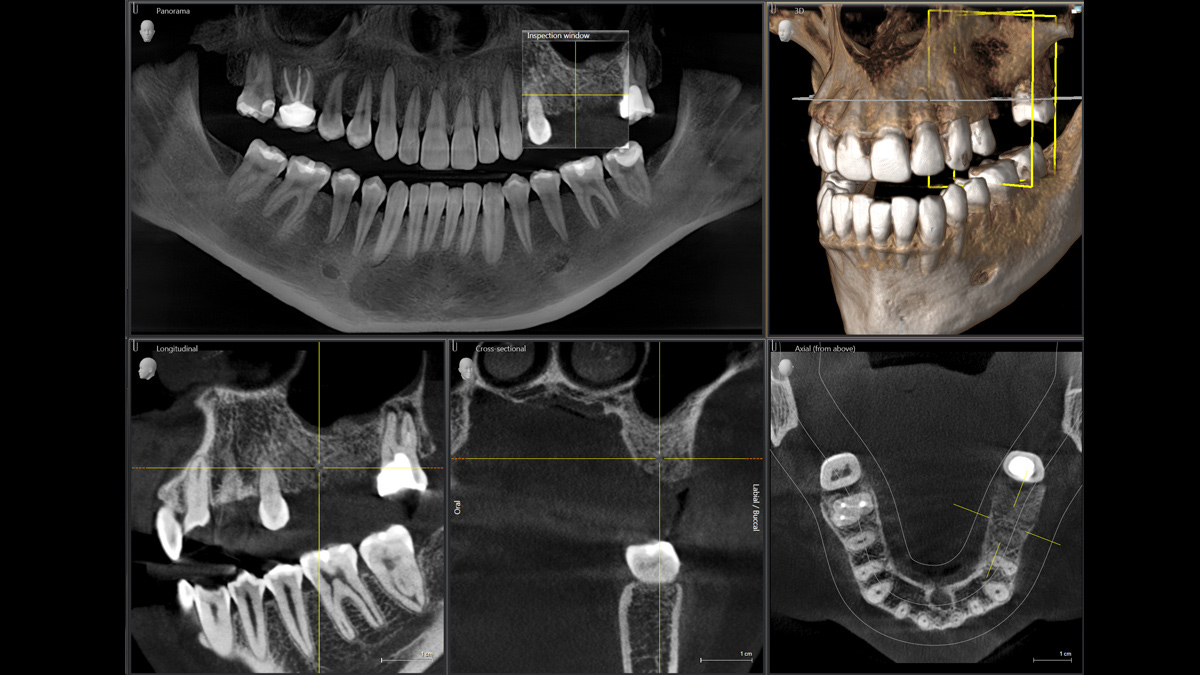

La tecnología 3D se está estableciendo cada vez más en los consultorios dentales en todo el mundo. Para diagnósticos más precisos y explicaciones del tratamiento, los rayos X en 3D ofrecen varias ventajas. Ya sea para dientes superpuestos, recorridos inesperados de los canales de los nervios, raíces ocultas o anomalías de las articulaciones temporomandibulares, las imágenes en 3D tienen un valor inestimable para un gran número de diagnósticos.

Orthophos SL 3D ofrece una gran variedad de opciones para satisfacer estas necesidades: diferentes tamaños de volumen donde elegir, modos HD/SD/Dosis bajas de radiación y un software inteligente e intuitivo para aprovechar al máximo las imágenes obtenidas y vincularlas directamente al tratamiento.

Galería de muestra de imágenes panorámicas 3D

Orthophos SL 3D en la práctica